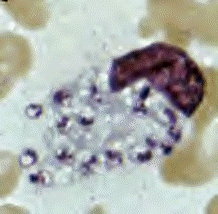

• Leishmania tropica amastigotes from a skin touch preparation.

• in B, amastigotes are being freed from a rupturing macrophage.  Patient with history of travel to Egypt, Africa, and the Middle East.

• Culture in NNN medium followed by isoenzyme analysis identified the species as L. tropica minor.-CDC http://www.dpd.cdc.gov/DPDx/HTML/Leishmaniasis.htm